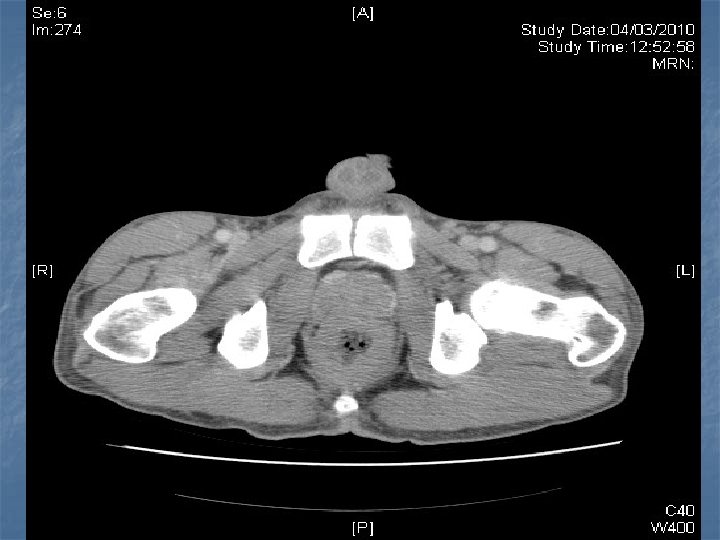

n n n PRETREATMENT INVESTIGATIONS: FBC, Renal and liver function, LDH, urate, Ig. GS. Histology review. Marrow aspirate+trephine (cytogenetics, immunology) CD 4 , HIV viral load. CT Scans. (MR Brain) (PET scan ) Echo / LVEF CMV, Hep B+C, Toxoplasma serology MAI screen. LP for CSF cytology +/- intrathecal Rx. (DLBC , Burkitt, Plasmablastic).

n n n PRIMARY CNS LYMPHOMA Typically occurs with marked immunosuppression CD 4<50. Marked reduction in incidence post HAART. Always EBV positive DLBC NHL. Commonly multifocal brain lesions. n High dose methotrexate iv Followed by brain XRT. n Poor prognosis survival months to 1 -2 years. n